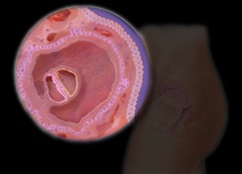

Mert 4-5 napon a megtermékenyített petesejt bejut a méhbe. Ekkorra az asszony már kifejlesztett egy embrió, amely körülbelül 100 sejt.

Implantáció a méhfal történik elején a harmadik héten. Miután ez a felfogás befejeződött. A mozgalom a méh és csatolja annak falán - a legveszélyesebb szakasza a magzat fejlődése az első hónapban.

Az első hónapban az implantáció után a folyamat kezdődik aktív képződése a magzat. Kezd kialakulni a chorion - a jövő placenta, magzatburok - elődje a membránok és a köldökzsinórt. A fejlesztés a magzat az első hónapban a terhesség kezdődik a kialakulását a három embrionális levelek. Mindegyikük jelentése rudimentum egyes szervekben és szövetekben.